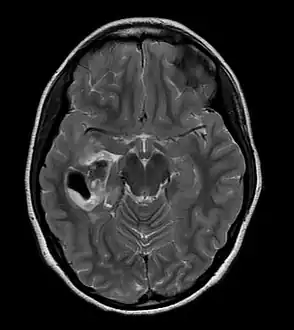

PXA as visualized on an MRI -